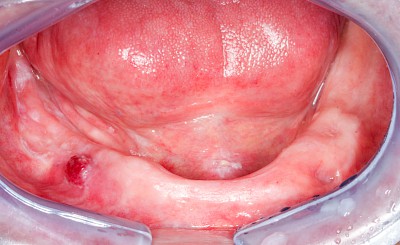

Mukositis bei Chemotherapie oder bei Strahlentherapie im Kopf-Hals-Bereich

Im Rahmen von Chemotherapie oder Strahlentherapie im Kopf-Hals-Bereich kann es zu schweren Entzündungen der Mundschleimhäute kommen (Mukositis).

Die chemo- bzw. strahleninduzierte Mukositis ist gekennzeichnet durch:

- Starke Schmerzen

- Großflächige Rötungen, z.T. mit Blutungen

- Großflächigen Blasen

- Schleimhautablösungen

Informationen zu Schleimhautentzündungen in Folge einer Chemo- bzw. Strahlentherapie im Kopf-Hals-Bereich finden Sie hier.